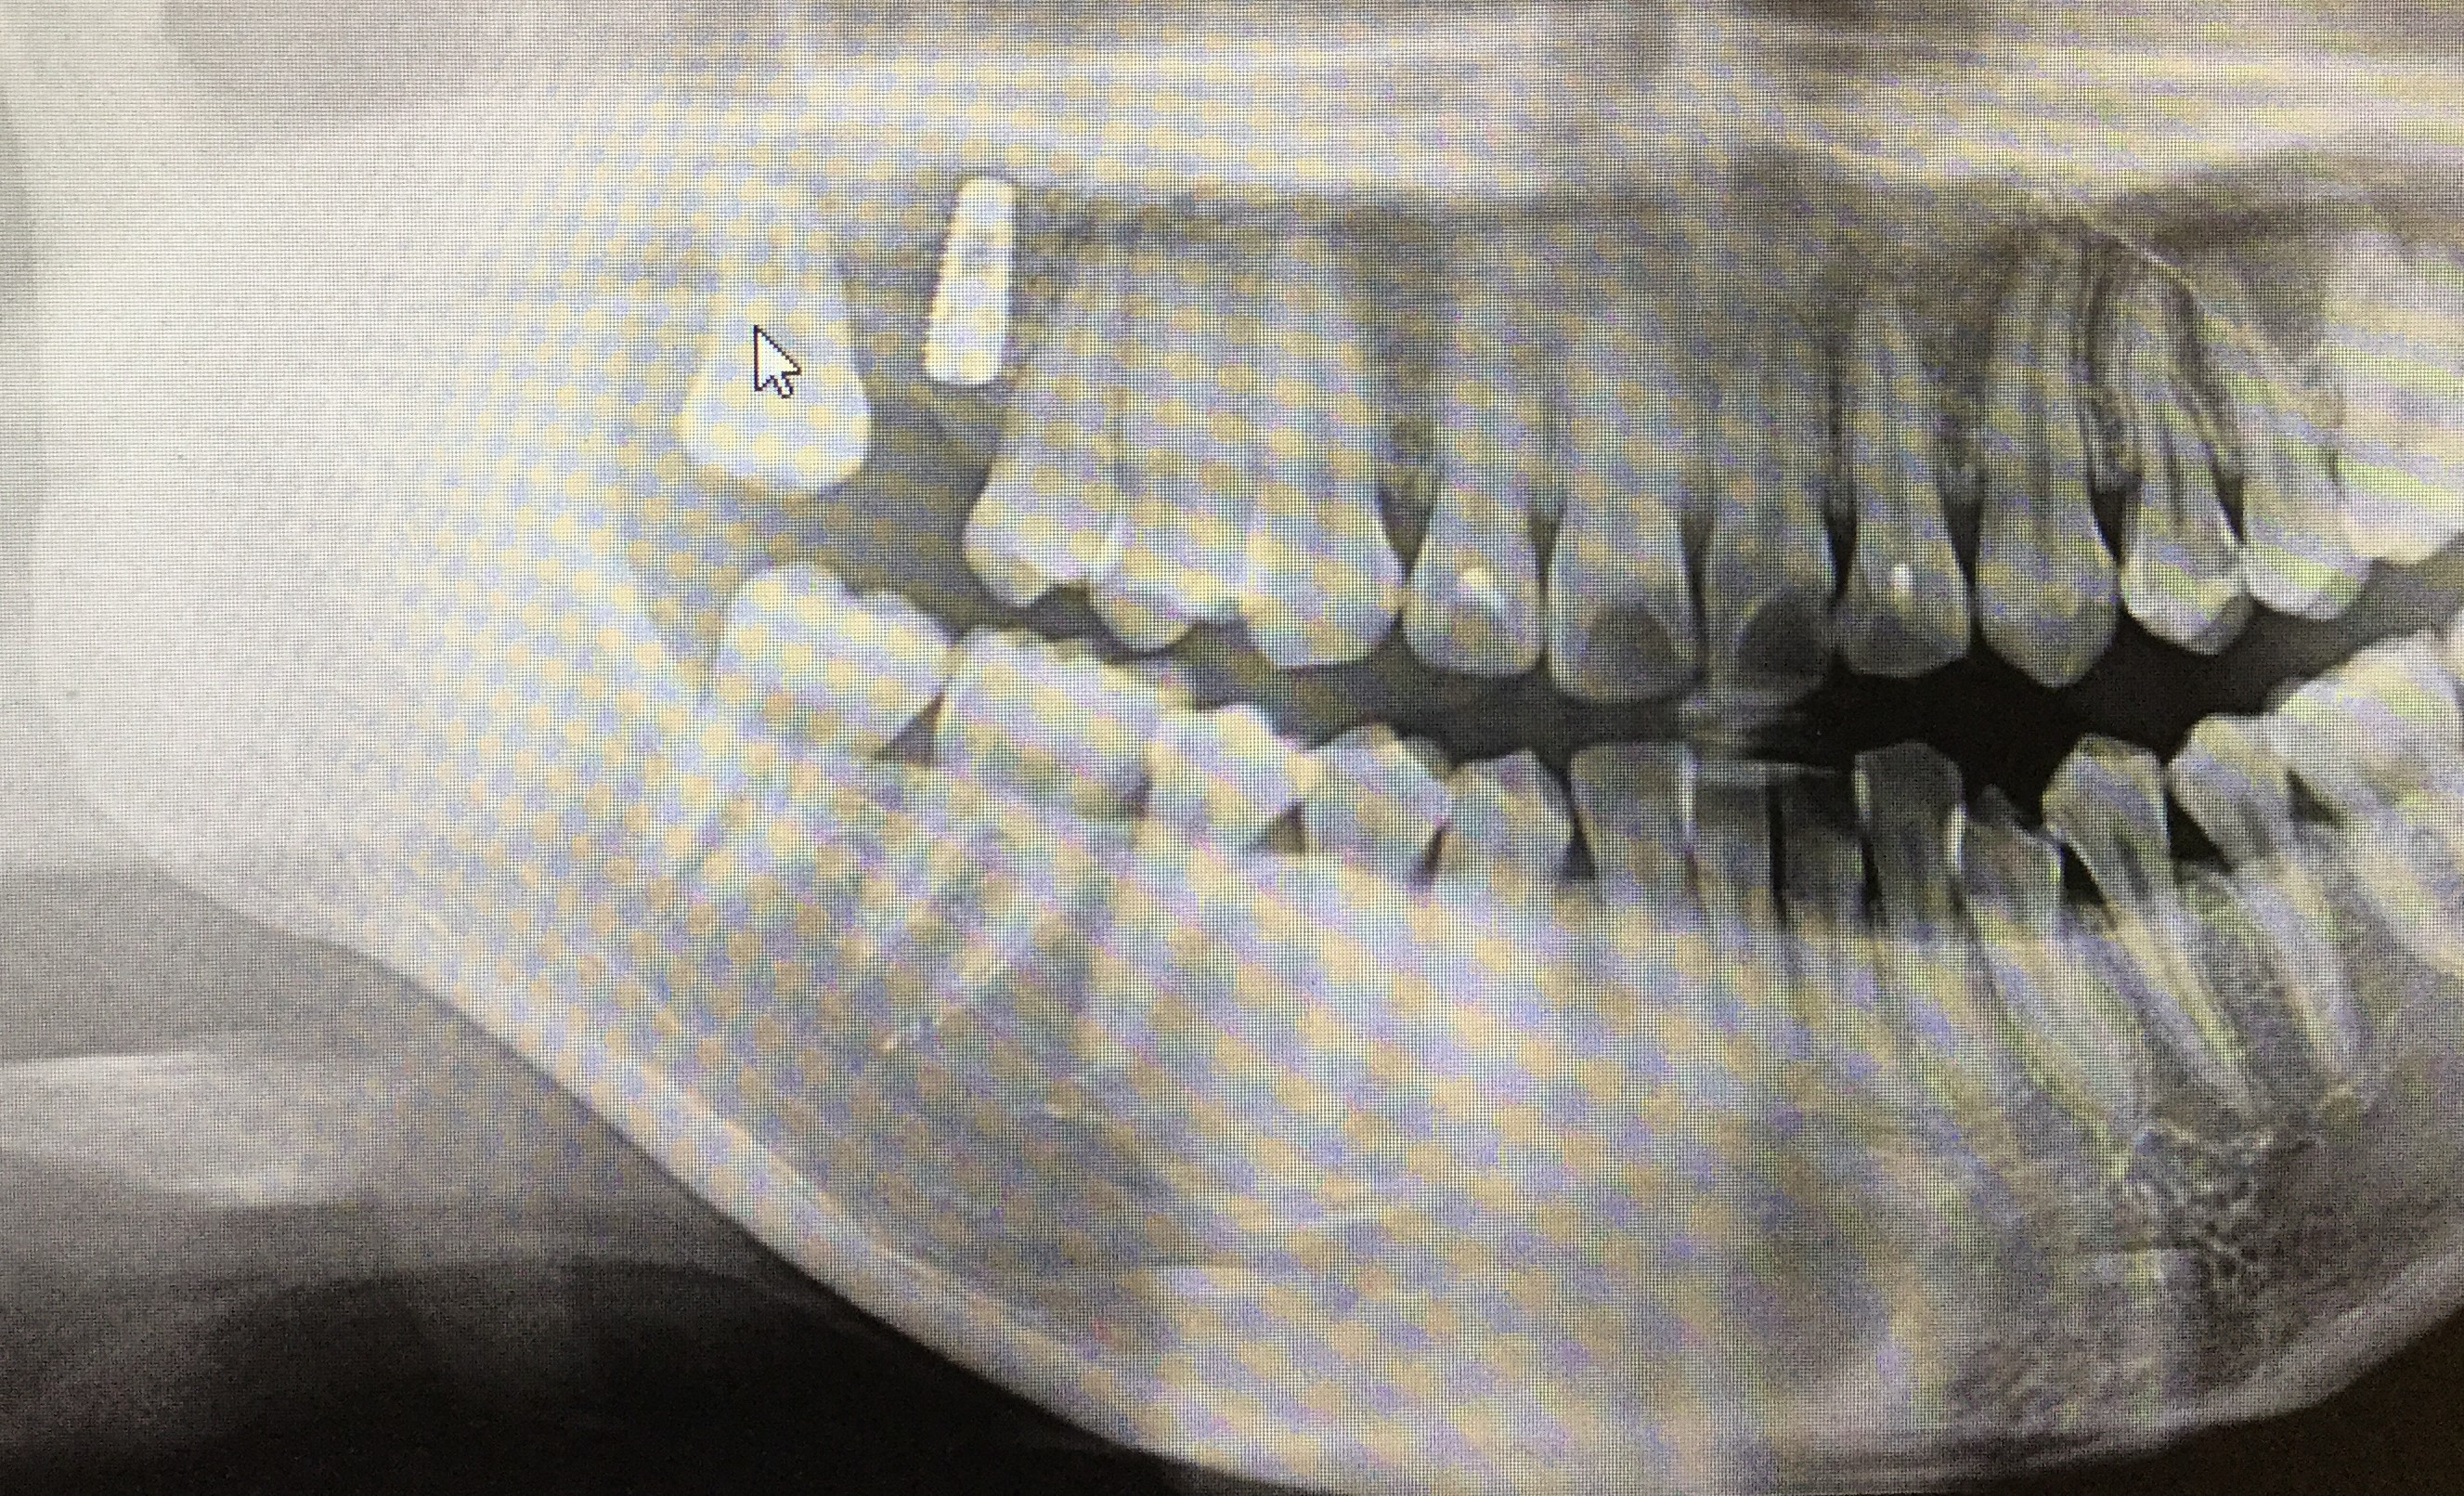

写真は一次オペが終わった後のレントゲンです♪

しっかりチタンのボルトが埋め込まれています(゜o゜)☆

痛みもなく経過も良好で2か月後に二次オペを行う予定です(^^)